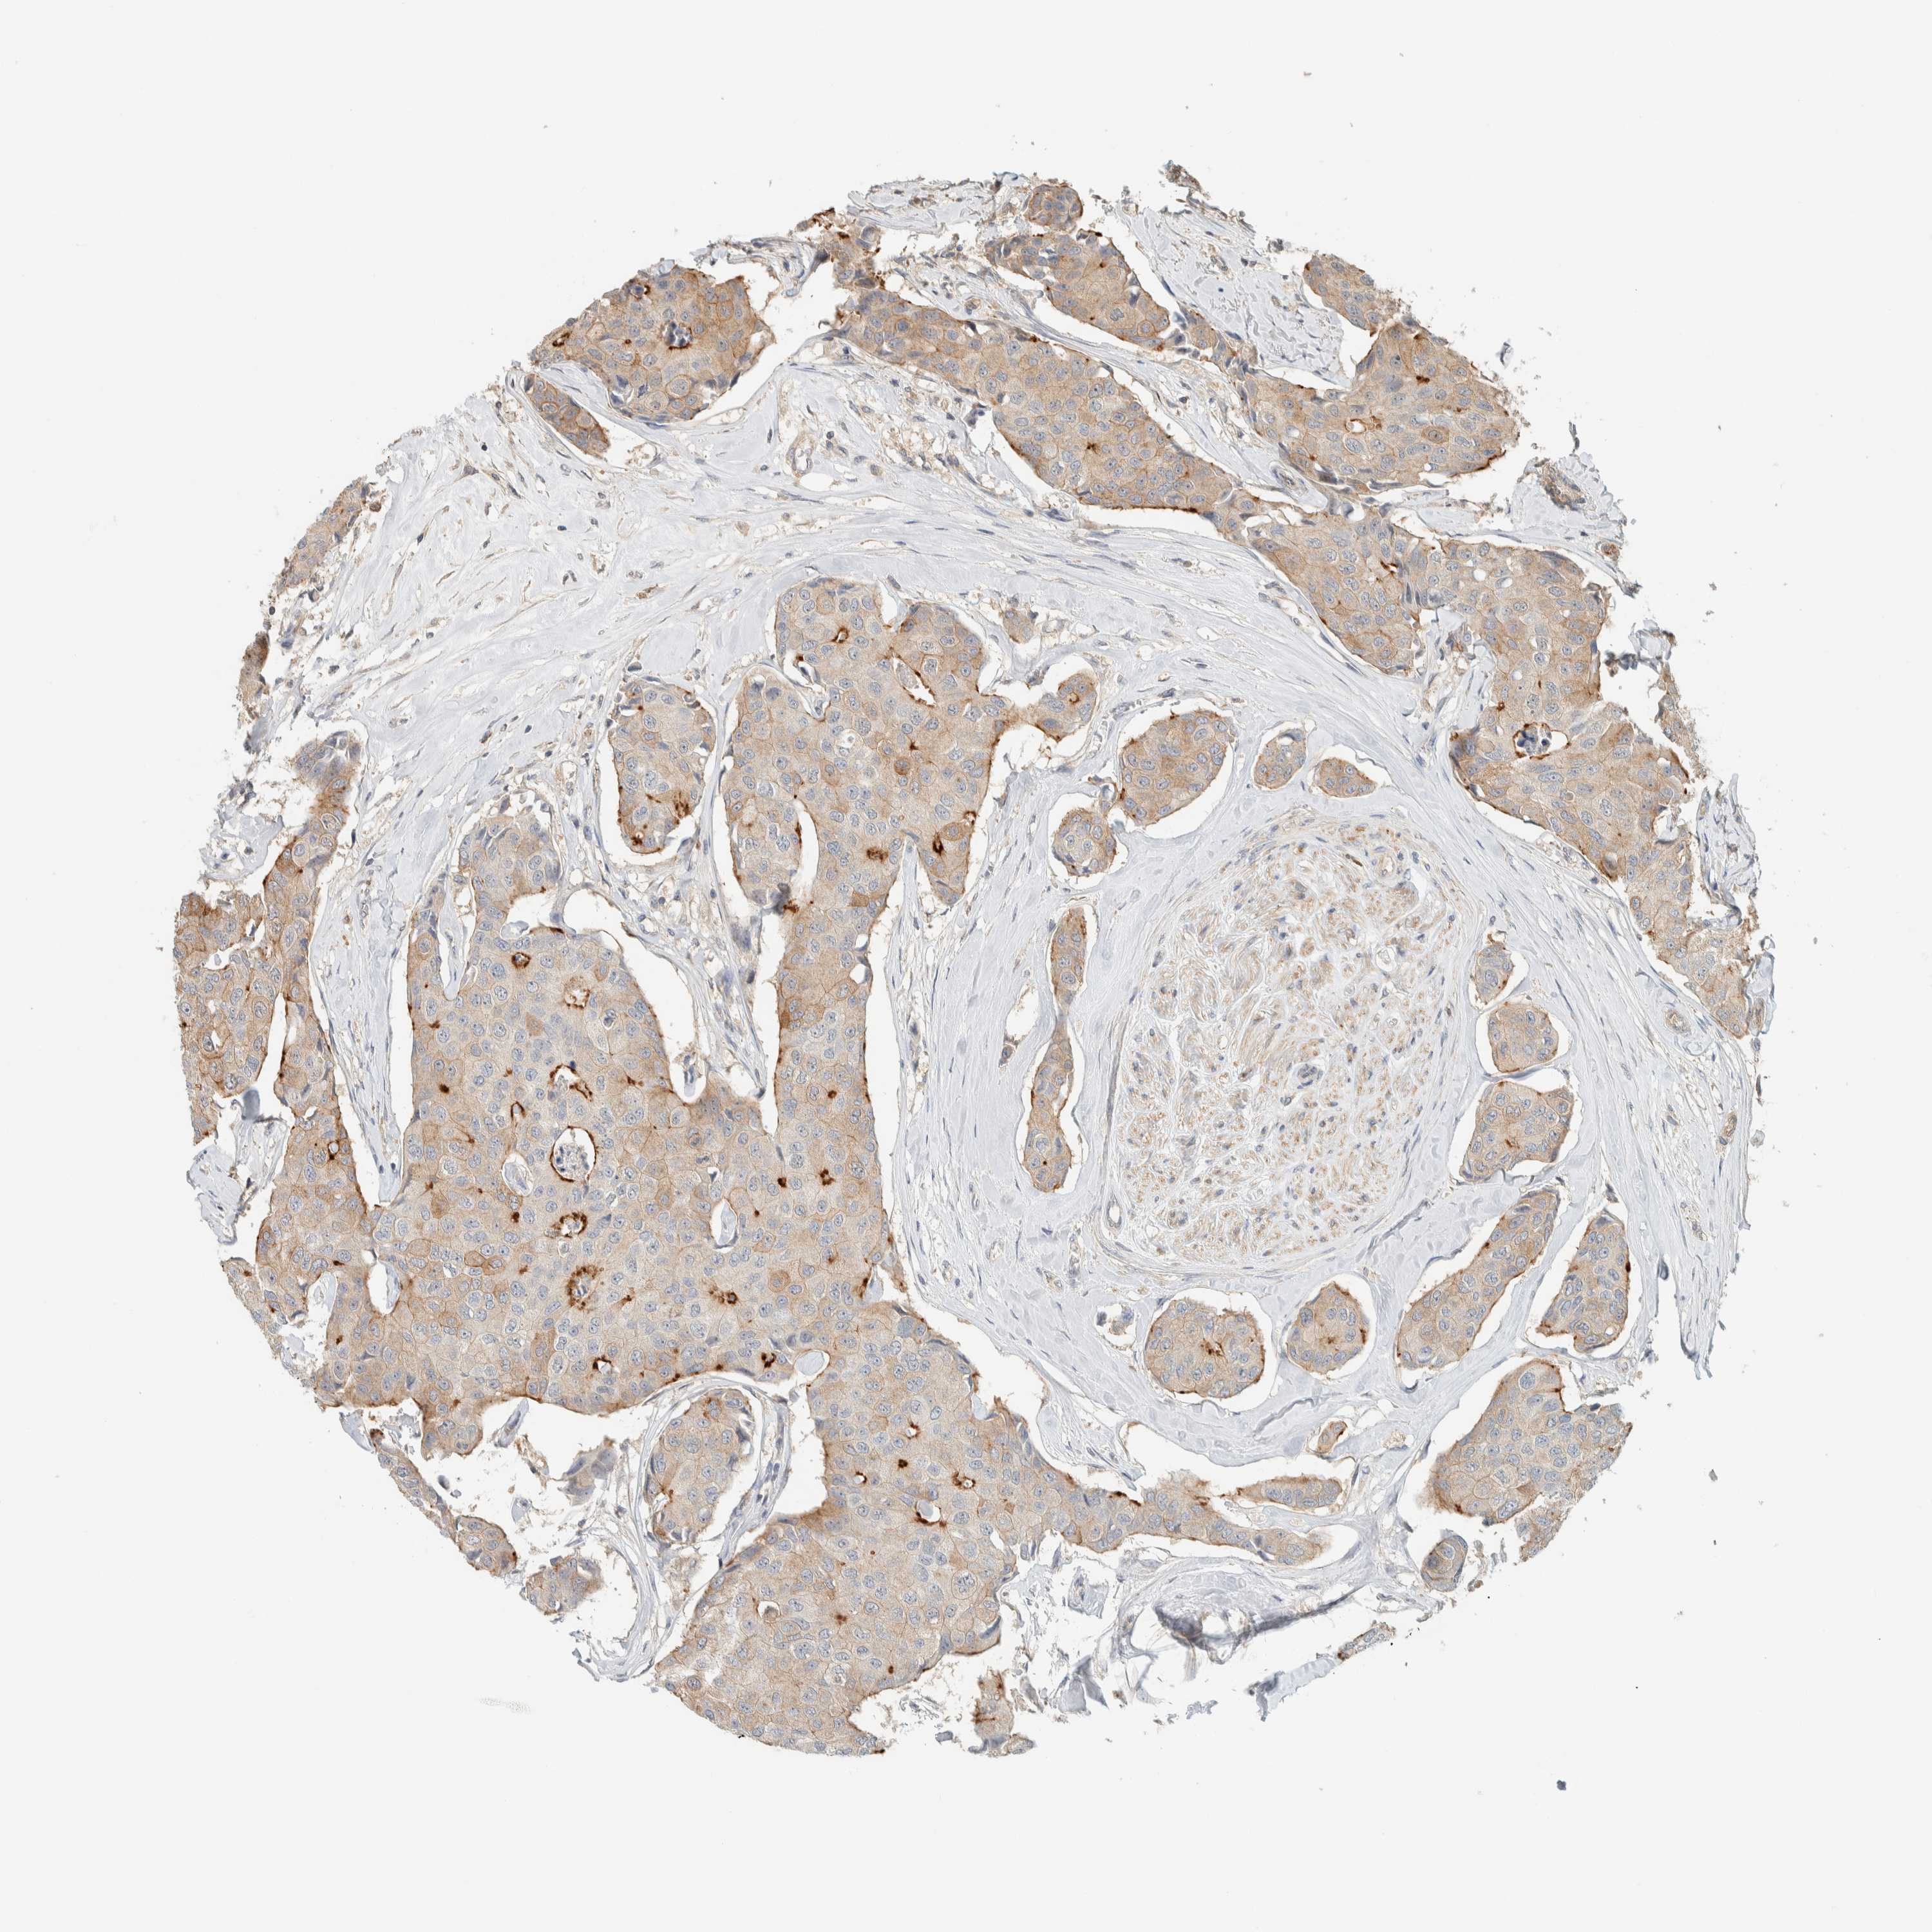

CANCER BREAST CANCER Show tissue menu

BRCA TCGA BRCA VALIDATION PROTEIN EXPRESSION